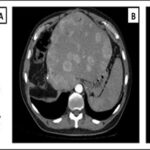

Paciente femenina de 50 años de edad con antecedentes de HTA. Anexo histerectomía total por carcinoma de útero, apendicetomía, colecistectomía, cesárea, resección de tumor basocelular. Derivada de Hospital Regional Dr. Luis Pasteur de Villa María de Córdoba el 21 de marzo de 2021 a Hospital Sanatorio Franchin por cuadro de hipoglicemias severas sintomáticas a repetición, con laboratorios clínicos donde se observó hipoglicemia asociada a hiperinsulinismo; el péptido C se encontraba elevado. Se realizó imágenes (TAC, RMN) que evidenciaban lesión en región de cabeza de páncreas medial con refuerzo arterial, compatibles en primera instancia con insulinoma. Se decide conducta quirúrgica debido a clínica, realizándose el día 27 de abril de 2021 duodeno pancreatectomía, evolucionó con fístula pancreática con requerimiento de octreotide. Posteriormente se realizó seguimiento de la paciente sin evidencia de síntomas de hiperinsulinismo, y en los controles radiológicos no se encontró recurrencia.

Estudio histopatológico reveló tumor neuroendocrino bien diferenciado grado 1, márgenes libres con ausencia de metástasis.